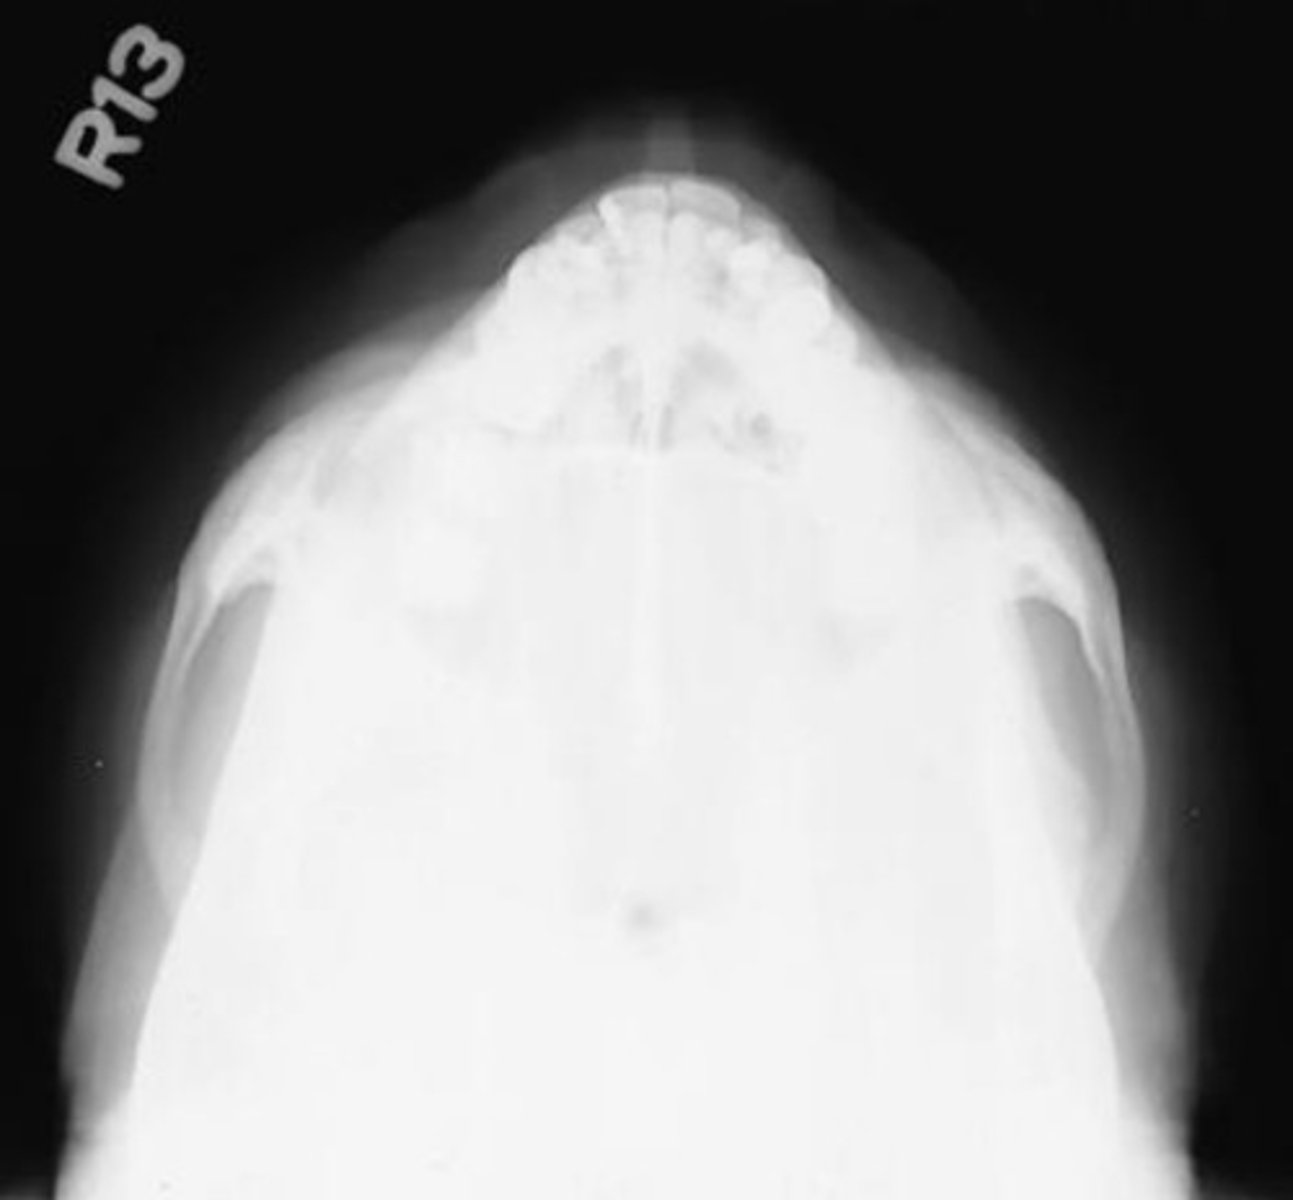

What projection and anatomy is demonstrated in the image below?

SMV of the zygomatic arches